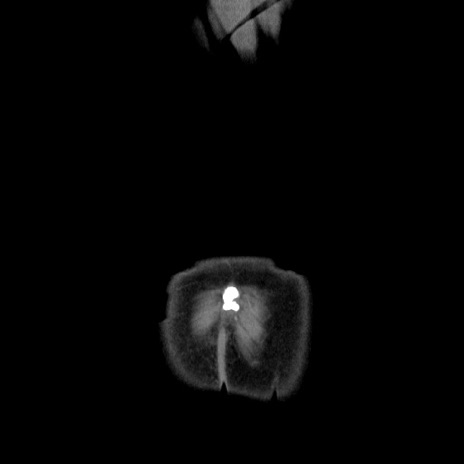

横断像